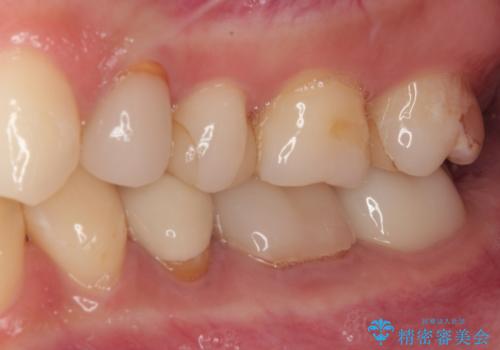

治療から9か月ほどが経過した時点で、違和感や痛みはなく、歯根端切除術を行った右下は、レントゲンでも良好な経過が確認できました。

今後も継続して観察を行っていくこととなります。